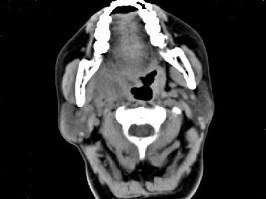

问题 女,52岁,咽喉部疼痛半个月,伴低热,CT如图所示,可能诊断为 ( )

选项 A、咽旁淋巴瘤 B、咽旁转移癌 C、咽部神经鞘瘤 D、鼻咽血管纤维瘤 E、咽旁脓肿

答案 E